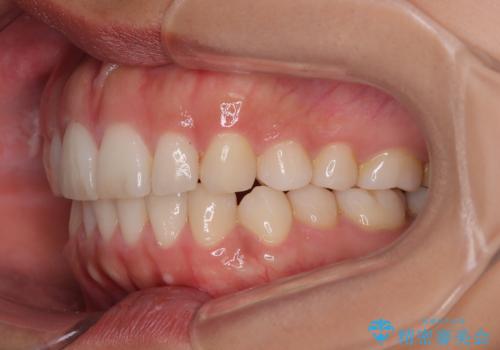

【モニター】突出した前歯 補助装置を併用したインビザライン矯正

- 上下前歯が非接触となり、前方に突出していることを気にして来院された患者様です。

咬合力が強く、全体的に歯がすり減っているため、インビザライン単独での上顎歯列移動は困難と判断し、補助装置により上顎歯列を後方移動させ、その後インビザラインにて仕上げていくこととしました。

補助装置なしでも改善できる可能性はありましたが、補助装置で確実性を上げ、短期間できっちりと仕上げることができました。